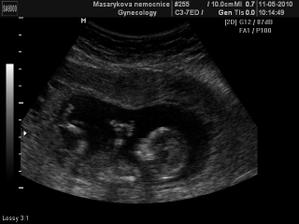

11.5. NT screening, jsem 13+5 a teď čekáme.....12.5. výsledky jsou v normě! 🙂